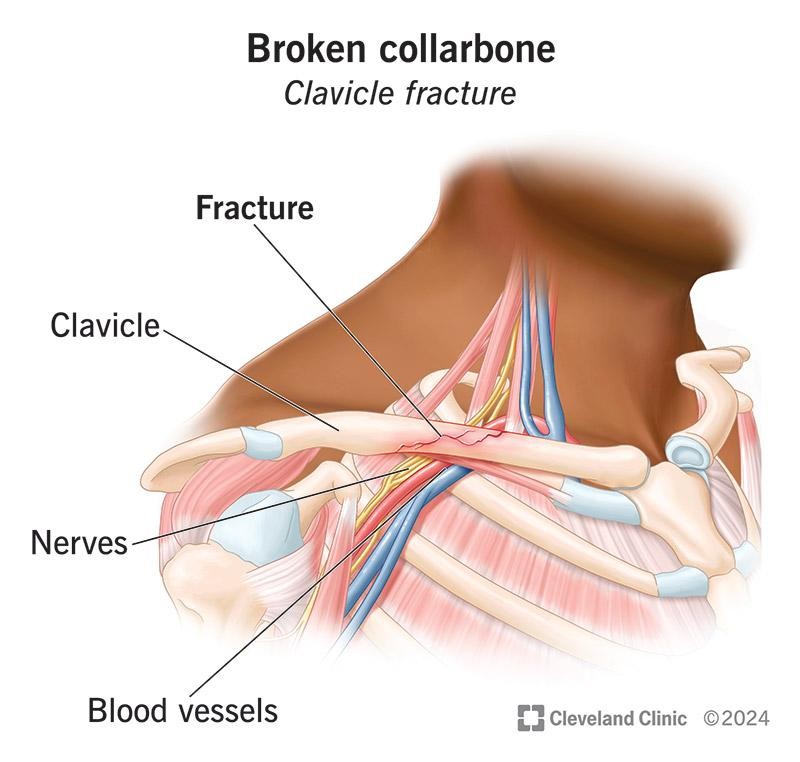

The clavicle lies above important nerves and blood vessels, which are carefully assessed in cases of fracture.

- Examination of nerve and blood vessel function

In some cases, the bone fragments may cause “tenting” of the skin, which requires urgent attention.

- Nerve or vessel injury